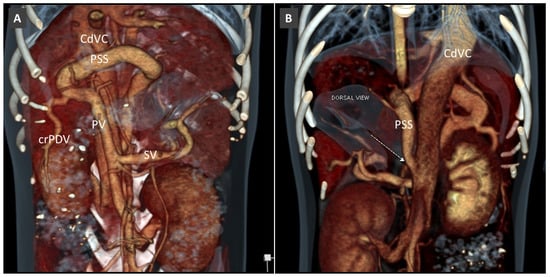

Congenital Portosystemic Shunt

3.8. Porto-Portal Collaterals or Cavernous Transformation of the Portal Vein